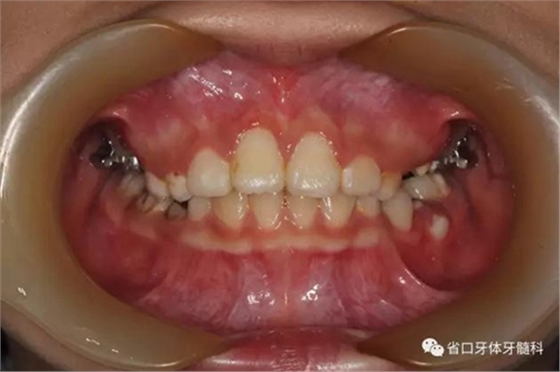

6個(gè)月后11牽引到位

治療過程:安裝上頜腭托式牽引裝置,局麻下翻瓣、開窗、暴露11牙冠,在牙齒腭側(cè)面粘接附件進(jìn)行輕力牽引,縫合。定期(2-3周)復(fù)診加力,待11唇面暴露后粘接前牙托槽,擴(kuò)展間隙的同時(shí)繼續(xù)進(jìn)行牽引、排齊。6個(gè)月后牽引到位,術(shù)后牙齒位置和牙髓活力均正常,牙齦形態(tài)良好,X線片顯示11牙軸基本正常,牙根發(fā)育良好。牽引結(jié)束后拆除前牙固定矯治器,由于前磨牙已開始替換,因此繼續(xù)戴用腭托進(jìn)行間隙保持。